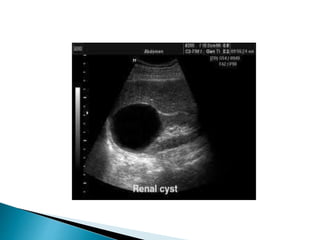

Uses high-frequency sound waves passed into the body and reflected

back in varying frequencies based on the composition of soft tissues.

Organs in the urinary system create characteristic ultrasonic images

that are electronically processed and displayed as an image.

Abnormalities, such as masses, malformations, or obstructions, can

be identified

Useful in differentiating between solid and fluid-filled masses.

ULTRASOUND